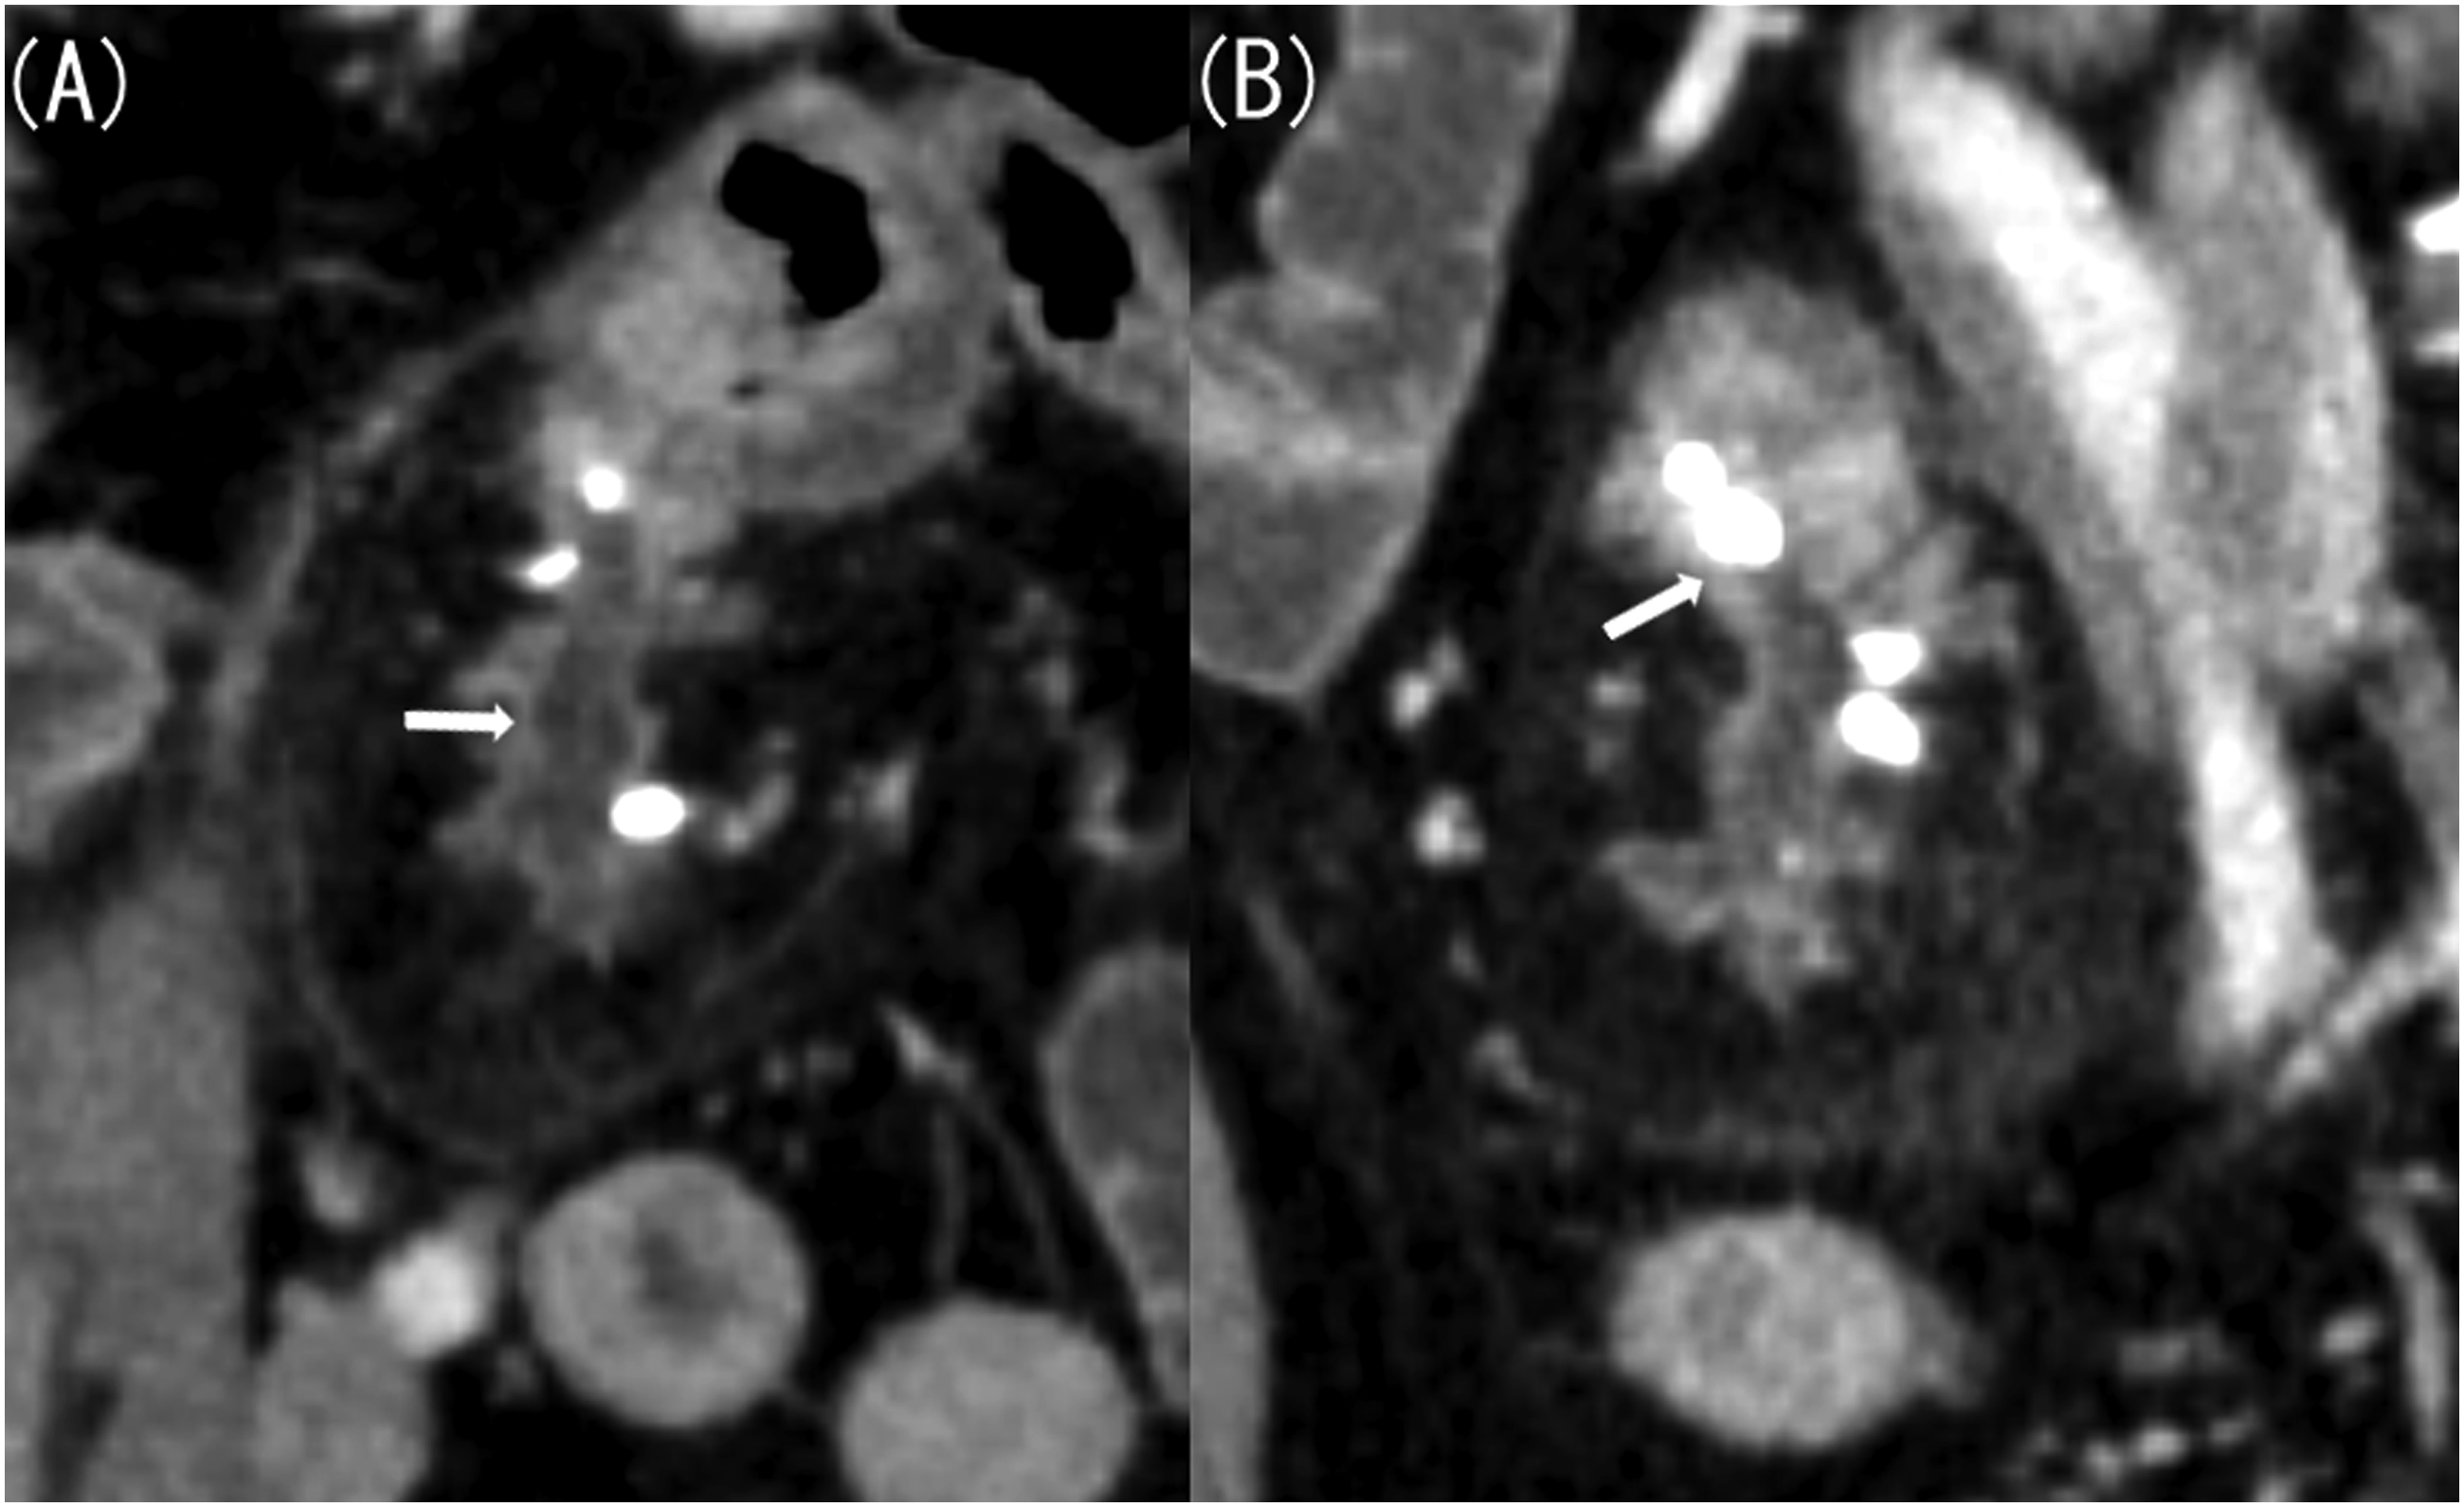

Next, we considered Meckel’s diverticulitis and confirmed the presence of Meckel’s diverticulum on previous CT scans. Contrast-enhanced CT performed 20 years ago revealed a 4 cm-long and 1.5 cm-wide lobulated structure in the left mesentery of the pelvis, resembling the pancreas (Figure 2(a)). CT scan performed 10 years ago showed that this structure had shrunk, appearing similar to an atrophied pancreas (Figure 2(b)). In a CT scan taken 4 years ago, it had further shrunk, with numerous calcifications (Figure 2(c)). The imaging findings were similar to a pancreatitis progressing to a chronic type observed in original pancreas. Additionally, the CT scan taken this time revealed dilatation of the luminal structure that corresponded to the main pancreatic duct (Figure 3(a)) and a stone being confined to the small intestine side (Figure 3(b)). This image finding indicated an acute exacerbation caused by pancreatic stone incarceration that typically occurs in chronic pancreatitis. The location of this structure was in the lower left abdomen on the CT scans taken 20 and 10 years ago, in the left abdomen on the CT scan taken 4 years ago, and in the lower right abdomen on the CT scan taken this time. A CT scan taken 20 years ago showed signs of acute pancreatitis of the native pancreas, including swelling and increased fat concentration in the surrounding area. However, there has been no change in size or shape of the native pancreas since the CT scan taken 10 years ago. (A) Contrast-enhanced computed tomography (CT) image taken 20 years ago (axial image, late phase). (B) Contrast-enhanced CT image taken 10 years ago (axial image, late phase). (C) Contrast-enhanced CT image taken 4 years ago (axial image, late phase). Contrast-enhanced CT taken 20 years ago revealed a pancreas-like lobulated structure measuring 4 cm-long and 1.5 cm-wide located in the left mesentery of the pelvis (A, arrow). Contrast-enhanced CT taken 10 years ago showed that the structure had shrunk, resembling an atrophied pancreas (B, arrow). Additionally, contrast-enhanced CT performed 4 years ago showed that the structure had further shrunk, with numerous calcifications (C, arrow). (A) Contrast-enhanced computed tomography (CT) image taken this time (coronal image, late phase). (B) Contrast-enhanced CT image taken this time (sagittal image, late phase). Compared with the CT result obtained 4 years ago, the luminal structure corresponding to the main pancreatic duct was dilated, with a stone confined to the small intestine side.